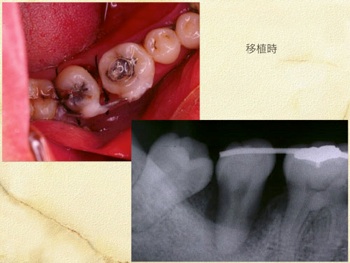

当クリニックでは自家歯牙移植を用いて、失われた歯牙を補う治療を行なっております。

自家歯牙移植の歴史は古く、近年の研究で歯牙、歯根膜へ配慮し施術することでその成績は格段に上がっております。

当クリニックでは約14年前より行なっており、約90%の成功率です。(尚10%の中には途中未来院になり判別不可能となった方も含まれますことをご理解ください。)

適応となる方は様々な条件により限られますが、適切に行なえば皆様に大きなメリットを提供できる治療方法です。